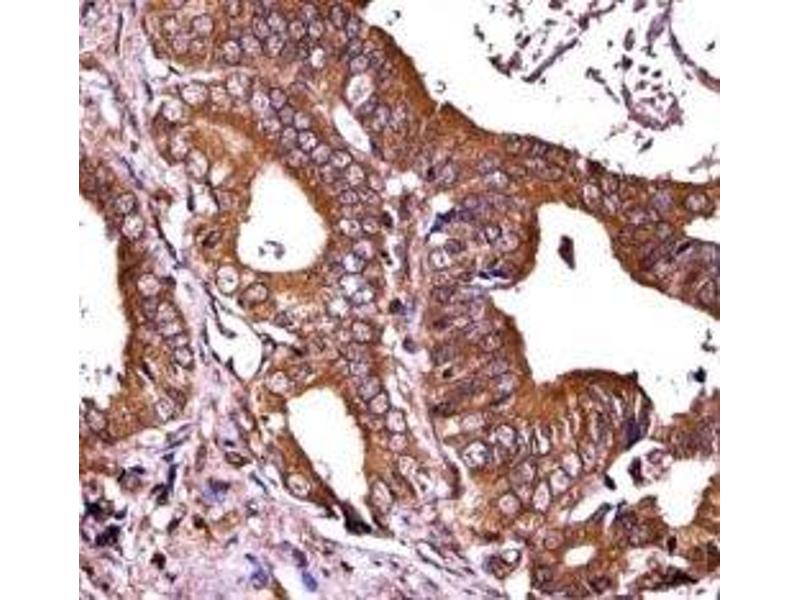

Titration of the RIPK1 antibody may be required due to differences in protocols and secondary/substrate sensitivity.\. Western blot: 1:1000,IHC (Paraffin): 1:10-1:50